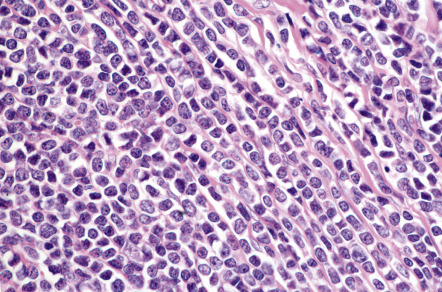

In DLBCLLT, a dense diffuse infiltrate is seen within the dermis and subcutis. The infiltrate usually involves the entire papillary dermis extending to the dermal–epidermal junction. Involvement of the epidermis by clusters of large atypical cells, simulating the Pautrier microabscesses found in cutaneous T-cell lymphoma, can be observed in some cases (B-cell epidermotropism), representing a potential diagnostic pitfall . The neoplastic infiltrate consists predominantly of immunoblasts (large round cells with abundant cytoplasm and prominent nucleoli) and centroblasts ( Fig. 119.11 ). Of note, cases of pCBCLs with a predominance of large cleaved cells (i.e. large centrocytes) are classified among the PCFCLs (see above) . Reactive small lymphocytes are usually few in number, and mitoses are frequent. The common finding of immunoglobulin gene hypermutations is evidence that DLBCLLT is a large cell lymphoma, representing post germinal center lymphocytes that originated from lymphocytes of the germinal center.

Neoplastic cells are positive for B-cell markers (CD20, CD79a, PAX-5, IgM), but there can be (partial) loss of antigen expression. Bcl-2, MUM-1 (see above), FOX-P1, and MYC are expressed by neoplastic cells in most patients . These markers are useful in the differential diagnosis of DLBCLLT from PCFCL, diffuse type; in the latter, Bcl-2, MUM-1, and FOX-P1 are usually either negative or expressed by a small minority of cells ( Fig. 119.12 ). The tumors demonstrate monoclonal rearrangement of IGH . The interchromosomal 14;18 translocation is not present. An algorithmic approach to the diagnosis of cutaneous diffuse large B-cell lymphomas is provided in Fig. 119.13 . The differential expression of lymphoid markers in various types of diffuse large B-cell lymphoma with cutaneous involvement is summarized in Table 119.3 .